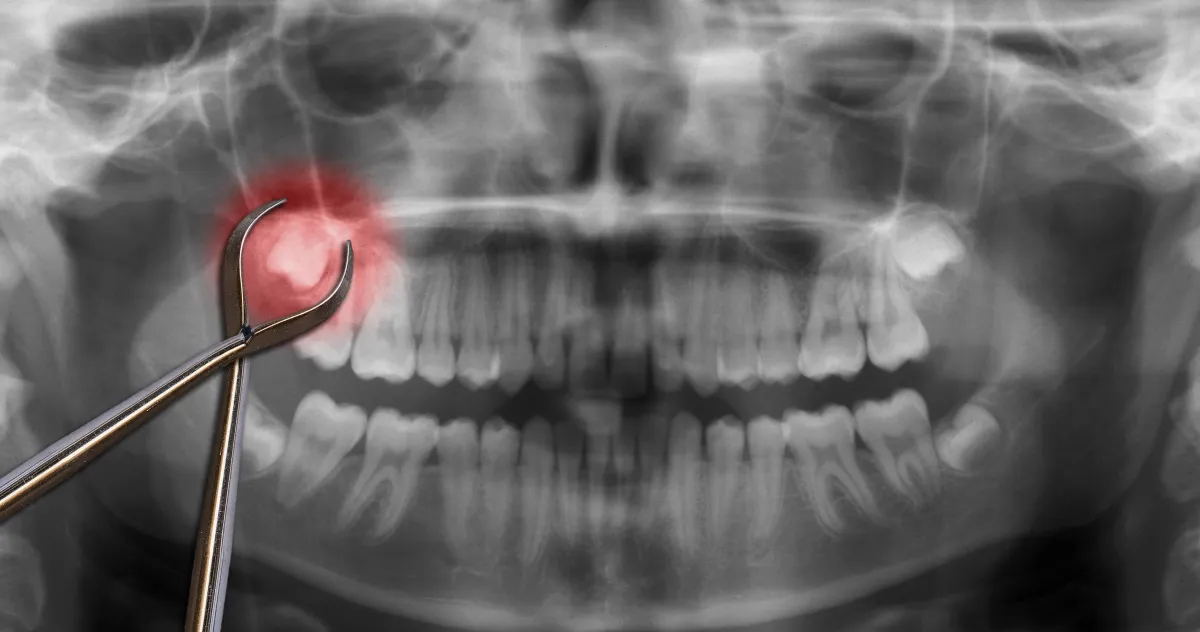

Emergency Dentist East Plano | Same-Day Emergency Dental Care

East Plano emergencies often come with real-life constraints: family schedules, school pickups, work commitments, and the hope that maybe the pain will “just calm down.” The problem is that dental emergencies don’t run on hope. Pain escalates. Swelling can appear. A cracked tooth can worsen. And the best time to address it is usually earlier than you think.

If you’re searching for an emergency dentist in East Plano, you want a same-day plan, clear answers, and a team that takes urgency seriously—without turning everything into a confusing sales pitch.

People Also Ask: Is gum swelling a dental emergency?

It can be. Swelling may signal infection and should be evaluated quickly—especially if it’s spreading, painful, or paired with fever.

Common East Plano emergencies

Severe toothaches that keep you awake

Broken teeth or cracked fillings

Crowns/fillings falling out

Swollen gums/facial swelling

Abscess symptoms (drainage/bad taste)

Trauma from accidents or sports

What an emergency visit looks like

Emergency visits focus on solving the immediate problem:

Exam + symptom review

X-rays if needed

Stabilization: stop pain and protect the tooth

Same-day treatment when appropriate or a fast plan forward

Emergency dentistry is about preventing escalation. That’s what saves teeth and reduces total cost.